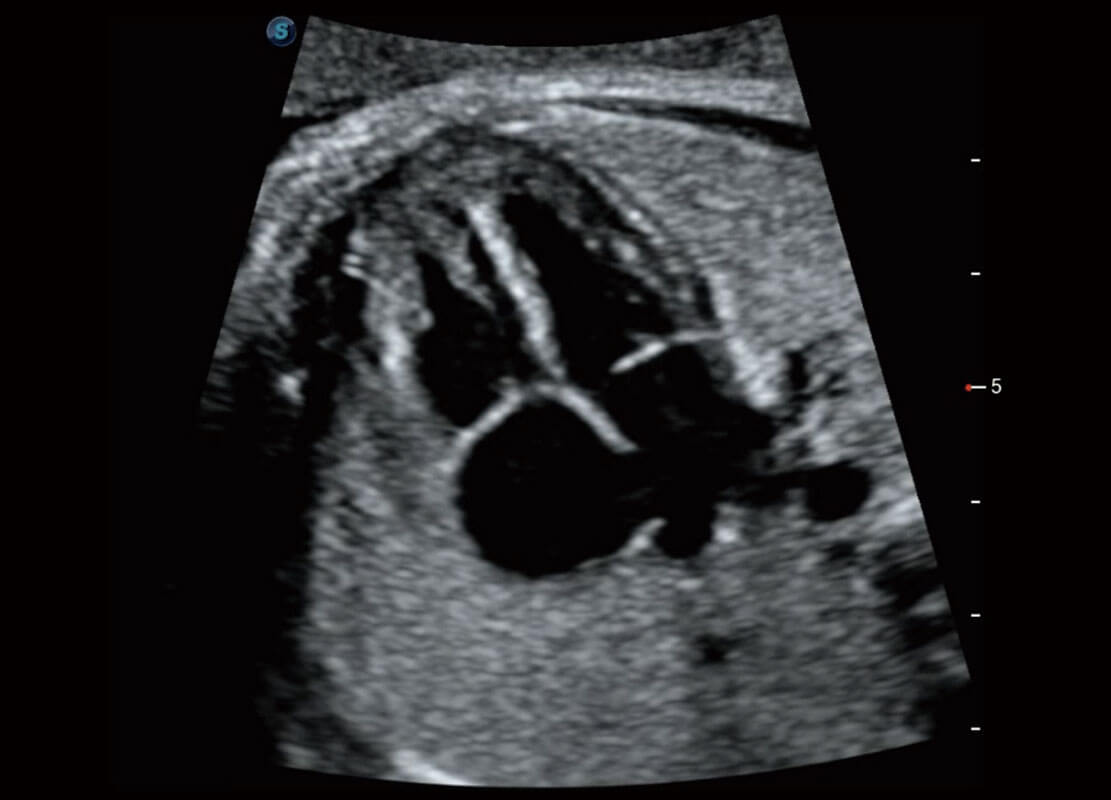

• 四腔切面

• 四腔心血流

• 右室双出口

• 胎心容积成像